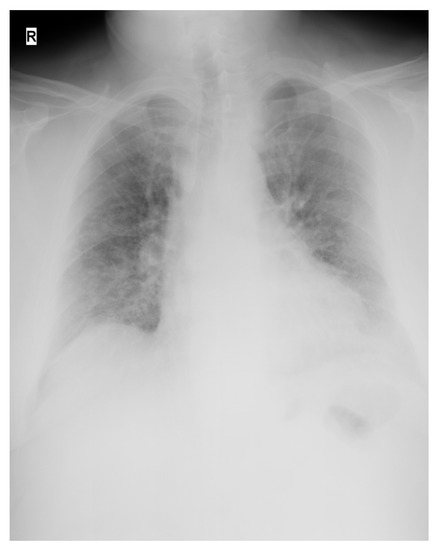

The Successful Recovery of a Critically Ill COVID-19 Patient, Following the Combination of Therapeutic Plasma Exchange and Convalescent Plasma Transfusion: A Case Report

With an intricate symptom pattern involving a dysregulated host response to infection, the severe acute respiratory syndrome coronavirus 2 (SARS-CoV-2) can cause severe inflammation and cytokine storms, acute respiratory distress syndrome, coagulopathy, multi-organ failure, and finally death. The uniqueness of this case report [...] Read more.

With an intricate symptom pattern involving a dysregulated host response to infection, the severe acute respiratory syndrome coronavirus 2 (SARS-CoV-2) can cause severe inflammation and cytokine storms, acute respiratory distress syndrome, coagulopathy, multi-organ failure, and finally death. The uniqueness of this case report lies in the nature of the therapeutic intervention performed. While numerous studies are available on both the use of therapeutic plasma exchange in coronavirus disease 2019 (COVID-19) patients and convalescent plasma transfusion as separate treatment methods, there is very little information regarding the combination of these procedures. We present the case of a 52-year-old male, unvaccinated for COVID-19, who tested positive on reverse transcriptase polymerase chain reaction for SARS-CoV-2 for the first time and presented in the emergency room with fever, chills, severe cough, tachypnea, tachycardia, and dyspnea that started two days before presentation. Upon rapid assessment, the patient showed signs of acute respiratory failure, so it was decided to transfer the patient to the intensive care unit, COVID-19 ward, after preliminary radiological examination. For the next 24 days, the patient was stationed in the intensive care unit, where he was closely monitored and treated. Invasive mechanical ventilation was required following the initial worsening of his respiratory status. We performed therapeutic plasma exchange on the first day of his stay in the intensive care unit, and immediately after the procedure, the patient was transfused with 500 mL of convalescent plasma from healthy donors. The patient’s condition improved over the next few days, which led to the cessation of mechanical ventilation and, after treating the superinfection, the patient was discharged home, making a full recovery. The early initiation of therapeutic plasma exchange followed by transfusion of convalescent plasma in severe and critical forms of COVID-19 may reduce the risk of the progression of the disease and ultimately reduce the risk of negative outcomes in a selected group of patients. Full article